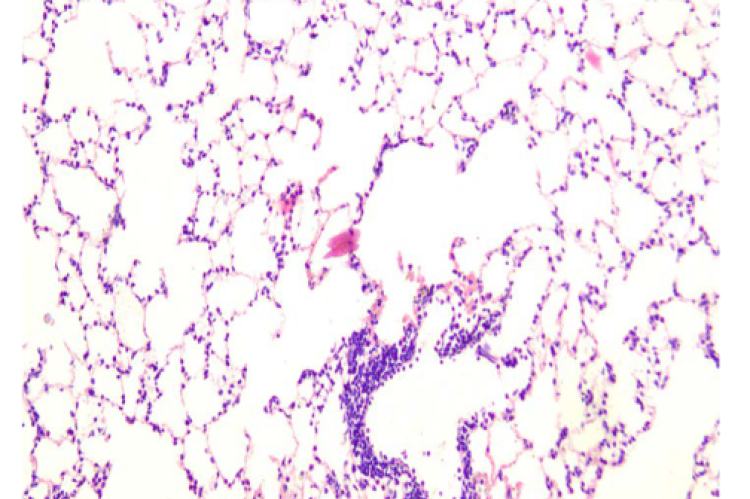

ArticleViewAbstractPharmacognosy Journal,2025,17,5,566-576.DOI:10.5530/pj.2025.17.70Published:September 2025Type:Original ArticleAcute Toxicity Study of the Crude Aqueous Extract of Tribulus terrestris Dried Fruit with Potential Diuretic EffectAmruth Kiran, Praveen Kumar S E, Tatiyana Mandal, K Ganesh Shenoy, Vasudev R Pai, Swati Sharma, and Arul Amuthan Amruth Kiran1, Praveen Kumar S E2, Tatiyana Mandal1, K Ganesh Shenoy1, Vasudev R Pai3, Swati Sharma4, Arul Amuthan1,5,* 1Division of Pharmacology, Department of Basic Medical Sciences, Manipal Academy of Higher Education, Manipal, India 2Department of Pharmacology, Manipal Tata Medical College, Manipal Academy of Higher Education, Manipal, INDIA 3Department of Pharmacognosy, Manipal College of Pharmaceutical Sciences, Manipal Academy of Higher Education, Manipal, INDIA 4Department of Pathology, Kasturba Medical College, Manipal Academy of Higher Education, Manipal, INDIA 5Division of Siddha, Centre for Integrative Medicine and Research (CIMR), Manipal Academy of Higher Education, Manipal, India Abstract:Introduction: Tribulus terrestris is an important medicinal plant used in Indian traditional medicine, the crude aqueous extract of the plant is primarily used to induce diuresis for treating cardiovascular diseases and managing renal stones, etc... The safe dose and adverse effect profile of the extract was not explored adequately in preclinical studies. Hence, the present study was undertaken. Methods: The acute toxicity was assessed based on the OECD guideline number 425: Acute Oral Toxicity – Up-and-Down-Procedure. A total of 11 animals were used in the study. Initially, one animal was administered with a dosage of 2000 mg/kg; and as the animal survived, four more animals were dosed and were observed for survival and other possible adverse drug reactions. The animals' body weight was measured before experimenting and at the end of the study. Biochemical and haematological examinations were done on normal control and test groups. Animals from the test group were sacrificed, and histopathological examinations of the vital organs were carried out. Results: No signs of toxicity or changes in the behaviour were observed in the treatment group. As all the animals survived, it was decided that the LD50 was greater than 2000 mg/kg. However, the changes observed with platelets, total cholesterol and LDL were within the normal limits. Histological examination of the vital organs did not reveal any changes in the architecture of the organs. Conclusion: Our study demonstrated that the crude aqueous extract of Tribulus terrestris dried fruit does not cause toxicity under the 2000 mg/kg dose limit. Keywords:acute toxicity study, crude aqueous extract, Indian traditional medicine, Siddha system of medicine, Tribulus terrestris, Wistar RatsView:PDF (538.92 KB) PDF Images Histopathology of lung tissue consisting of alveoli and bronchioles ‹ Antioxidant Activity and Isolation of Xanthine Oxidase Inhibitor from Ruellia tuberosa L. Leaves up Antibacterial and Antioxidant Activity of Black Mulberry (Morus nigra L.) Extract for Acne Treatment ›